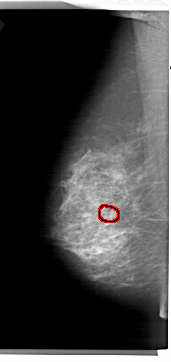

A_1461_1.LEFT_MLO

LEFT_MLO LINES 6871 PIXELS_PER_LINE 3241 BITS_PER_PIXEL 12 RESOLUTION 43.5 OVERLAY

FILE: A_1461_1.LEFT_MLO.OVERLAY

TOTAL_ABNORMALITIES 1

ABNORMALITY 1

LESION_TYPE CALCIFICATION TYPE AMORPHOUS DISTRIBUTION CLUSTERED

ASSESSMENT 4

SUBTLETY 4

PATHOLOGY BENIGN

TOTAL_OUTLINES 1

BOUNDARY